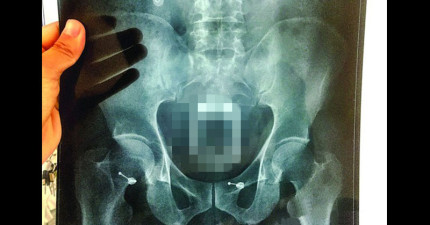

中國男子想出「超天才秘方」來治便秘,沒想到塞進去的東西讓醫生都嚇壞了!

June 2, 2015